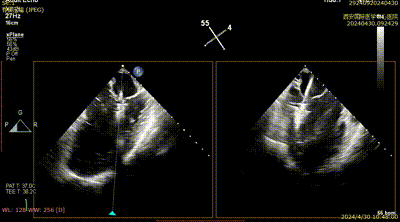

患者为75岁女性,因间断性心慌气短8个月,加重两月入院,既往腔隙性脑梗塞,乳腺癌30年,已治愈。心脏彩超提示:前叶长度:2.9cm,后叶长度:1.2cm,瓣口面积:4.5cm²,病变宽度:13mm。

心脏瓣膜介入团队术中在2区植入一枚二尖瓣夹,关闭二尖瓣夹时时刻关注瓣叶张力,并随时释放张力。患者术后反流降至1+,跨瓣压差为3mmHg。

术后二尖瓣反流评估

术后结果